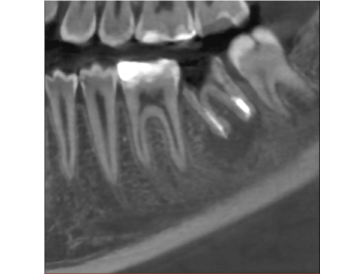

Технология ART-V - уменьшение артефактов

Артефакты от металлов мешают визуализации и естественным образом снижают достоверность диагностики. Четкие изображения дают вам меньше поводов волноваться и больше доверия к результатам диагностики при планировании имплантации. А также вам не составит труда планирование хирургического шаблона.

*ART-V новое название алгоритма коррекции артефактов от VATECH.